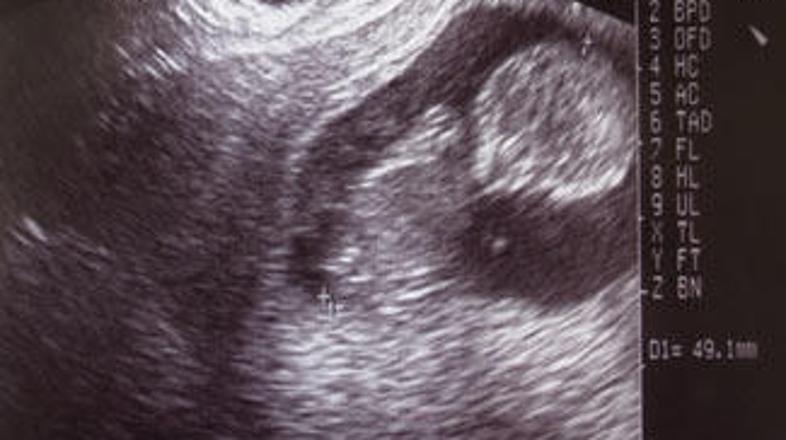

52,3 odstotka od 11.510 sodelujočih volivcev te katoliške državice med Švico in Avstrijo se je izreklo proti legalizaciji splava, potem ko je predlagani zakon predvideval, da bi bilo mogoče splav opraviti v prvih 12 tednih nosečnosti ali pa če bi bilo jasno, da se bo otrok rodil težko prizadet.